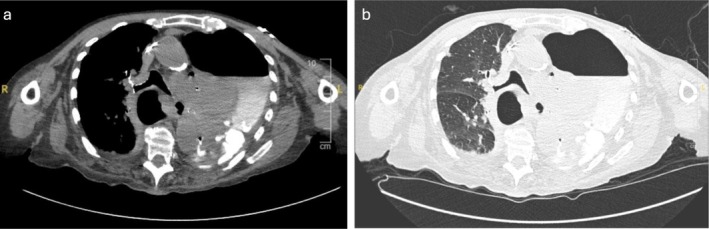

一名95岁女性因胸痛和呼吸困难就诊于急诊科。她有左侧紧张性气胸,继发于靠近胃-食管交界处的裂孔疝自发性破裂。这在以前的文献中没有描述过,因此,本报告的目的是引起临床医生的兴趣,并强调这种罕见的现象作为胸痛的裂孔疝患者的可能鉴别诊断。这也证明了在使用计算机断层扫描检查食管破裂时使用口服造影剂的重要性。

A 95-year-old female presented to the emergency department with chest pain and difficulty breathing. She had a left-sided tension hydropneumothorax secondary to a spontaneous rupture of a hiatus hernia close to the gastro-oesophageal junction. This has not previously been described in the literature and therefore, the purpose of this report is to pique clinicians' interest and highlight this rare phenomenon as a possible differential diagnosis in patients with a hiatus hernia who present with chest pain. It also demonstrates the importance of the use of oral contrast when using computerised tomography to investigate for oesophageal rupture.